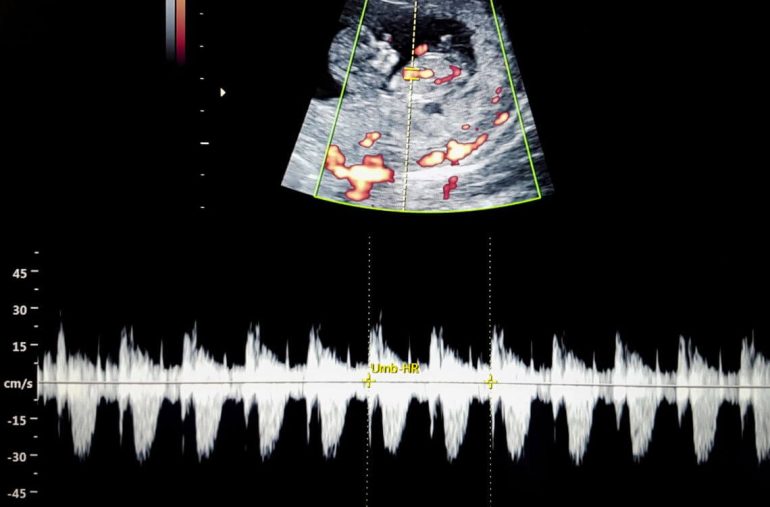

Pada usia kandungan 11 minggu ini bayi Mommy sudah sebesar ukuran bola golf. Bayi Mommy juga sudah boleh mula bernafas di dalam rahim. Bayi Mommy akan menyedut dan menghembus sejumlah kecil amniotik. Ini untuk membantu paru-paru bayi membesar dan berkembang.

Selain itu, hati bayi juga sudah mula menghasilkan sel darah merah yang berfungsi untuk menghantar oksigen ke seluruh tubuhnya. Wajah bayi Mommy juga akan mula terbentuk pada minggu ini. Pasti Mommy tertanya-tanya, bayi Mommy akan ikut muka Mommy ke Daddy ya?